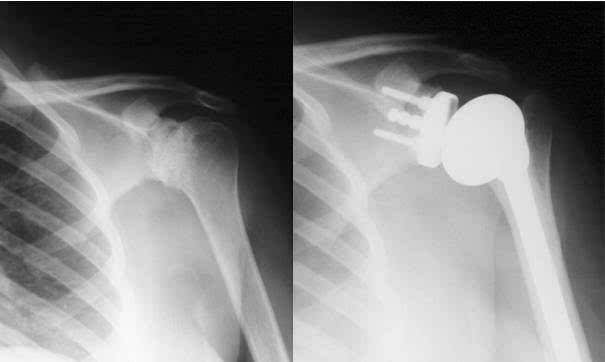

肩關(guān)節肩關(guān)節shoulderjoint由肩胛骨的關(guān)節盂和肱骨頭構成,屬球窩關(guān)節。

關(guān)節盂周緣有纖維軟骨環(huán)構成的盂緣附著(zhù),加深了關(guān)節窩。肱骨頭的關(guān)節面較大,關(guān)節盂的面積僅為關(guān)節頭的1/3或1/4,因此,肱骨頭的運動(dòng)幅度較大。

因為肱骨頭較大,呈球形,關(guān)節盂淺而小,肩關(guān)節僅包繞肱骨頭的1/3,關(guān)節囊薄而松弛,所以肩關(guān)節是人體運動(dòng)范圍最大而又最靈活的關(guān)節,它可做前屈、后伸、內收、外展、內旋、外肩關(guān)節是由肩胛骨的關(guān)節盂與肱骨頭組成,故又叫肩肱關(guān)節。 因為肱骨頭較大,呈球形,關(guān)節盂淺而小,僅包繞肱骨頭的1/3,關(guān)節囊薄而松弛,所以肩關(guān)節是人體運動(dòng)范圍最大而又最靈活的關(guān)節,它可做前屈、后伸、內收、外展、內旋、外旋以及環(huán)轉等運動(dòng)。

但肩關(guān)節的這個(gè)結構上的特點(diǎn)雖然保證了它的靈活性,但它的牢固穩定性都較其他關(guān)節為差,是全身大關(guān)節中結構最不穩固的關(guān)節。 最常見(jiàn)的是向肩關(guān)節的前下脫位,因為肩關(guān)節的上方有肩峰、喙突及連于其間的喙肩韌帶,可以防止肱骨頭向上脫位。

肩關(guān)節的前、后、上部都有肌肉、肌腱與關(guān)節囊纖維層愈合,增強了其牢固性。而只有關(guān)節囊的前下部沒(méi)有肌肉、肌腱的增強,這是肩關(guān)節的一個(gè)薄弱區。

因此當上肢外展時(shí),在外力作用下或跌倒時(shí),如上肢外展外旋后伸著(zhù)地,肱骨頭可沖破關(guān)節囊前下方的薄弱區,移出到肩胛骨的前方,造成肩關(guān)節前脫位。 這時(shí)患肩塌陷,失去圓形隆起的輪廓,形成所謂的“方肩”。